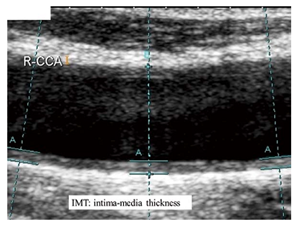

IMT was defined as the distance between the leading edge of the lumen-intima echo and the leading edge of the media-adventitia echo (Figure 1). At least 3 measurements were taken over a 1-cm length of each common carotid artery, and measurements from both sides were averaged to obtain the mean IMT. When plaque was present in the segment used for measuring the mean IMT, the plaque thickness was averaged into the mean IMT measurement.

Figure 1 R-CCA (Right common carotid artery). Definition of intima-media thickness